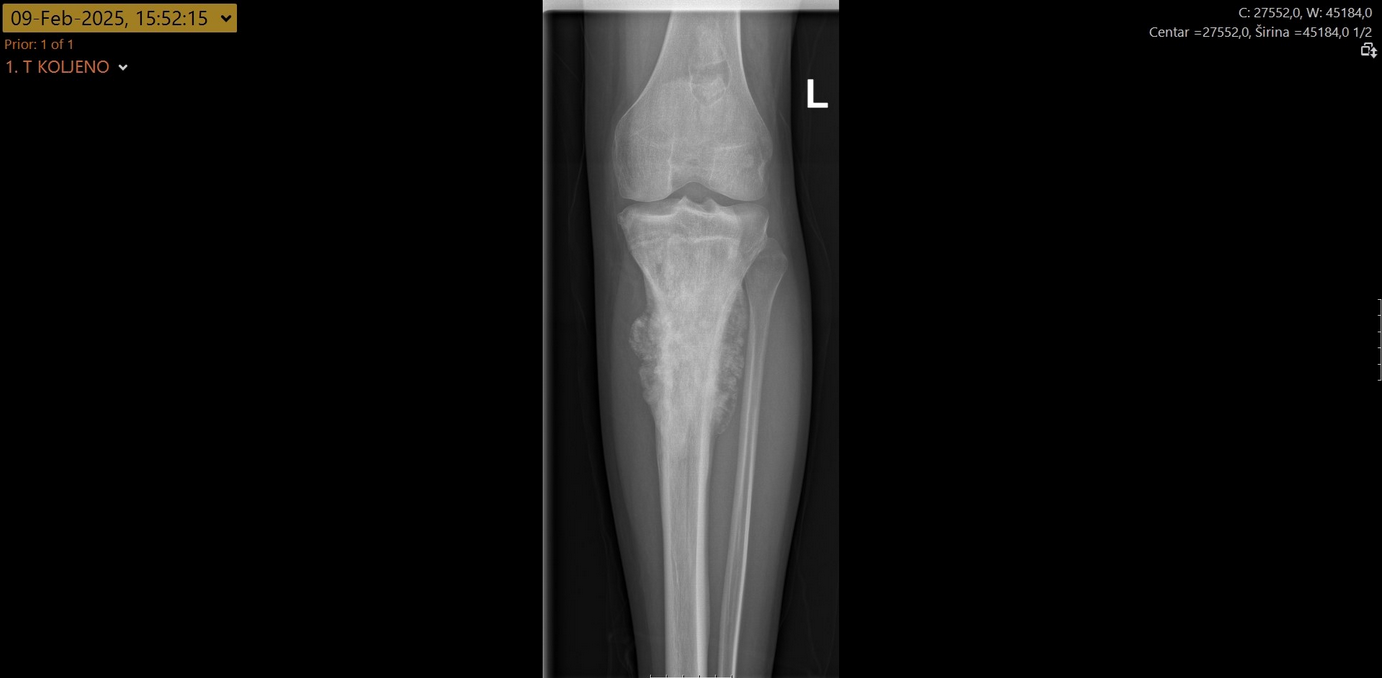

Na Zavodu za ortopediju i traumatologiju Kliničkog bolničkog centra Split po prvi put je obavljen zahvat odstranjenja izrazito malignog tumora osteosarkoma tibije.

Tijekom zahvata u potpunosti mu je odstranjen koljenski zglob te gornjih 17 cm goljenične kosti koji su zamijenjeni posebnom tumorskom protezom i nadomjestkom – implantatom za odstranjenu kost.